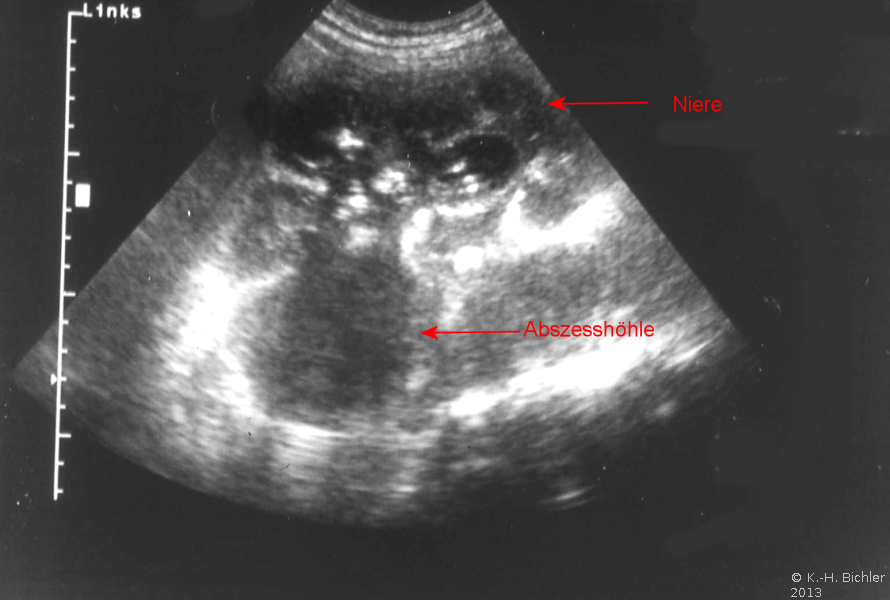

Die Abbildung zeigt als weiteres Beispiel die sonographische Darstellung eines ausgedehnten paranephritischen Abszesses (Abbildung 7).